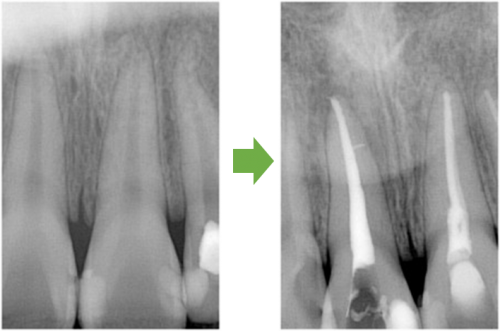

むし歯が神経に達しています。

むし歯を取り神経の管に穴を開けます。

神経の冠を拡げていきます。

神経の管を拡げ終えたら→最終的な薬を詰めます。